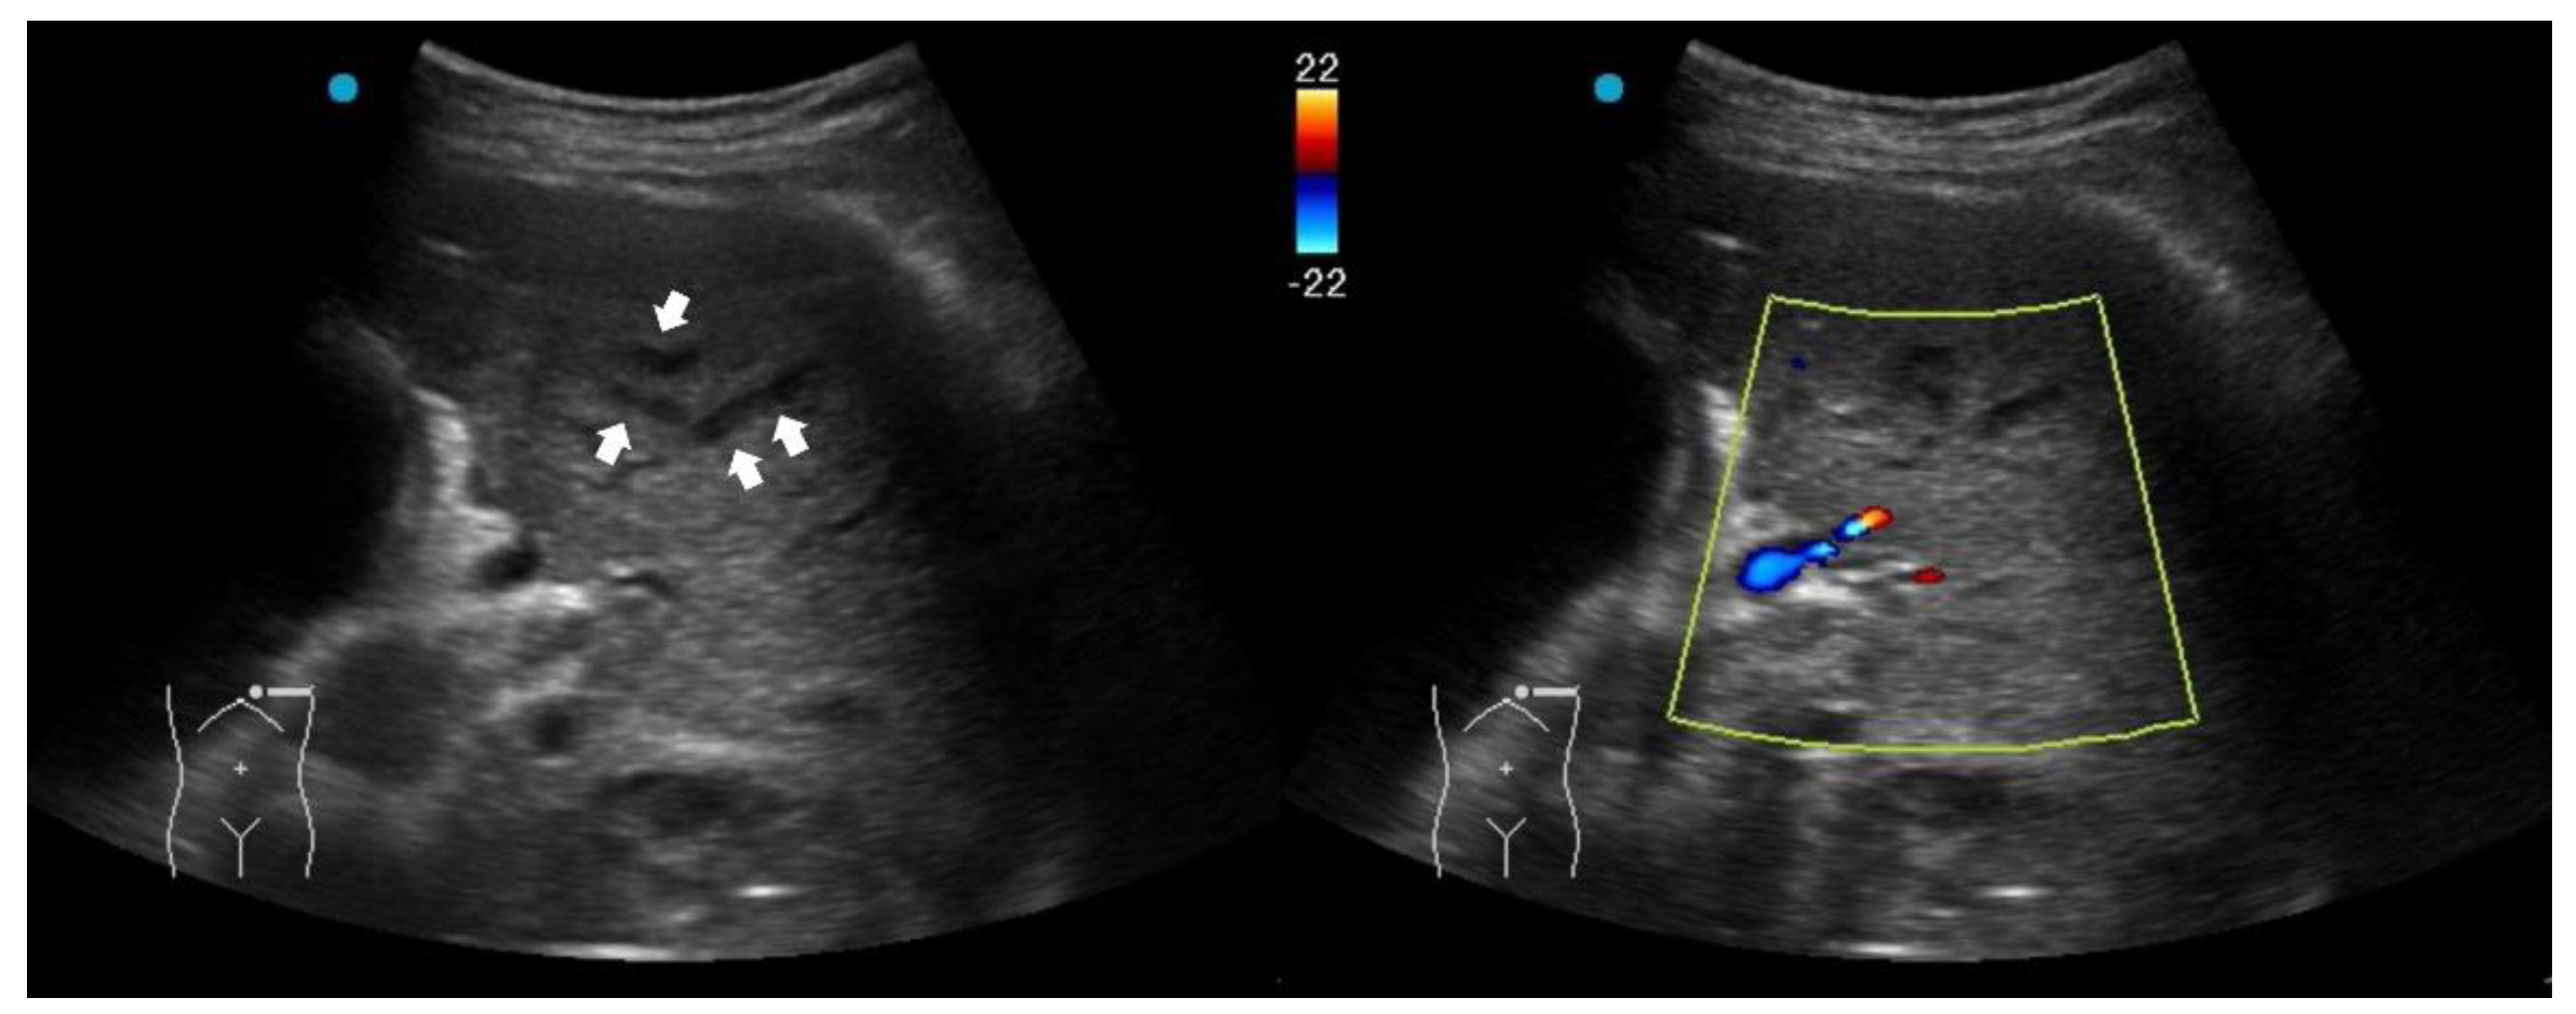

2.3. Red Flag Signs Related to Necrotizing Pneumonia

A study retrospectively reviewed 236 children with CAP. The perfusion of subpleural consolidation was classified into normal perfusion (homogenously distributed tree-like vascularity), decreased perfusion (less than 50% of an area with typical tree-like vascularity), and poor perfusion (no recognizable color Doppler flow) [28]. Poor perfusion had a positive predictive value of 100% and 81.8% for all necrotizing pneumonias and severe necrotizing pneumonias, respectively. It was also associated with an increased risk of pneumatocele formation and the subsequent requirement for surgical lung resection. However, the absence of color Doppler signals within consolidations has been scarcely studied in adult CAP and warrants further investigation in future research.

Another LUS sign of necrotizing pneumonia in children was the presence of a heterogeneous hypoechoic consolidation containing more hypoechoic confluent lesions [29]. These hypoechoic lesions were thought corresponding to necrotic cavities. Adult studies have shown that the presence of micro-abscesses or hypoechoic areas within consolidations may suggest necrotizing changes, prompting further confirmation with a repetitive CT in suspicious patients (Figure 3) [30,31].

Figure 3. Ultrasound findings in necrotizing pneumonia and corresponding computed tomography images: (A) Micro-abscesses; (B) Hypoechoic lesions within consolidations.